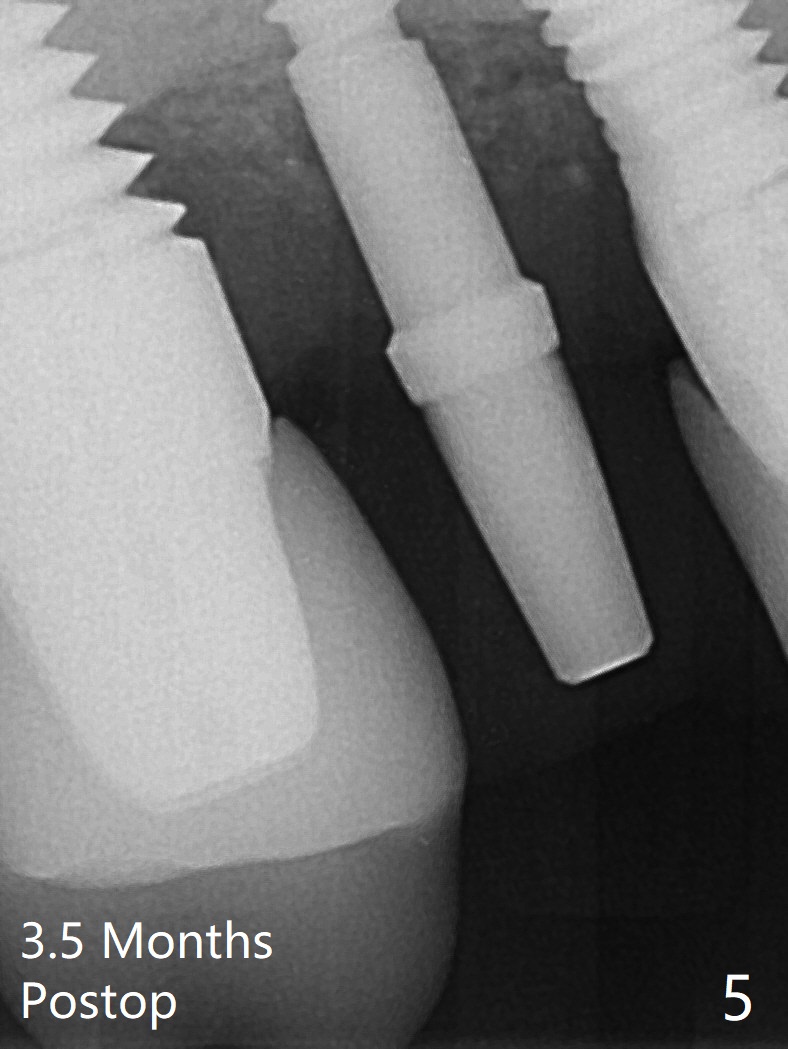

The osteotomy gap at #4 disappears 3.5 months post implant removal with bone graft; the mesiodistal space is 6.6 mm (Fig.1). Incision confirms disappearance of the osteotomy gap. A new osteotomy is established for 10 mm (Fig.2). A 2.5x10(4) mm 1-piece implant is placed with <50 Ncm; since the trimmed implant threads at #5 are exposed (Fig.3), Vanilla graft with Osteogen is placed mesial and distal to the new small implant (Fig.4 *). There is no bone loss 3.5 months postop (Fig.5,6). After cementation of the crown (Fig.7 C) with the thin abutment (*), the patient feels that the crown has mobility. The crown in fact has no clinical mobility; it cannot be removed. After occlusal equilibrium, the patient does not feel the same. The thin 1-piece implant must flex under heavy occlusion. The patient is a bruxer. There is no crestal bone resorption 4 months post cementation (8 months post cementation, Fig.8,9). There is no sign of periimplantitis anymore. The implant remains mobile and symptomatic (chewing pain) 14 months post cementation (Fig.10). There is no bone loss 2 years 4 months post cementation (Fig.11).